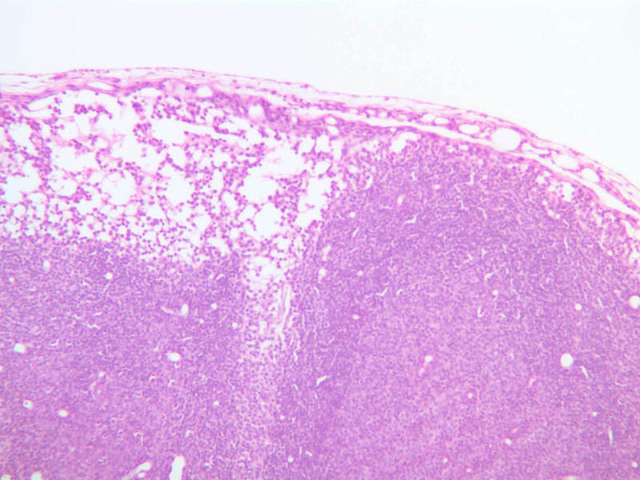

Sections through the spleen (slides A-36, aniline blue [2.5x, 10x, 20x-labeled, 40x] [2.5x, 10x-labeled, 20x-labeled, 40x]; A-37, retic [2.5x, 10x, 20x-labeled, 40x]; A- 37, H&E [2.5x-labeled, 10x, 20x, 40x]; A-38, H&E [10x, 20x, 40x]; A-39, H&E [2.5x, 10x, 20x, 40x]) show a thick investing capsule composed of collagenous tissue and smooth muscle, typically covered with mesothelium. In slide A-36 muscle and collagen are brightly stained. The capsule and mesothelium completely surround the organ and the fibrous portion enters the splenic substance at the hilus around the splenic arteries and veins forming trabeculae of fibromuscular tissue within the splenic substance. This fibromuscular tissue enables the spleen to expel blood by contracting. Identify trabeculae as fibrous partitions in the section and look for blood vessels within them.

Where the trabecular arteries pass into the splenic pulp, they become invested by a sleeve of lymphoid tissue. This lymphatic tissue collectively forms the white pulp of the spleen (A-36 [2.5x, 10x, 20x, 40x]). It also is referred to as the periarterial lymphatic sheath or PALS. On an H&E stained section (A-38 [2.5x, 10x, 20x, 40x] [2.5x, 10x, 20x, 40x]) the white pulp will appear as basophilic clumps of lymphoid cells. The arteries of the white pulp are called central arteries, although they may be displaced to one side of the lymphoid sleeve by the presence of a nodule. The majority of cells forming the PALS are T lymphocytes. In places the covering of lymphatic tissue is enlarged due to the presence of lymphoid nodules (splenic or Malphighian corpuscles) which are comprised predominantly of B lymphocytes.

The remainder of the cellular mass in the spleen is red pulp (A-38 [10x, 20x, 40x]), made up of red and white cells of the blood enmeshed in the reticular tissue of splenic cords and present in the splenic sinuses. After passing through the PALS, the trabecular arteries branch to form smaller arterial vessels known as penicillar arterioles which narrow, forming arterial capillaries that empty into the cords of the red pulp (open circulation) or into the venous sinuses (closed circulation). In the splenic sinuses the cells of the blood are exposed to red pulp macrophages. The splenic sinuses eventually become confluent to form veins that enter the trabeculae and gradually merge meeting in the hilus to form splenic veins.

Examine the composition of the red pulp tissue. The three dimensional structure of the red pulp is analogous to Swiss cheese with the holes being the venous sinuses and the cheese being the parenchyma (i.e. splenic cords). On slide A-36 which is stained with Mallory's aniline blue locate examples of the splenic sinuses ([2.5x, 10x, 20x, 40x-labeled] [10x, 20x, 40x]). The walls of the splenic sinuses consist of adjoining specialized endothelial cells whose nuclei in many cases stand out from the wall in a bead-like fashion. The basement membrane of the epithelial cells stains blue revealing the sinuses quite nicely. Usually the sinus lumen is filled with red cells and leukocytes. The skeletal framework of the cords is provided by a network of reticular fibers. As above, the reticular cells are best seen using a reticular fiber stain (slide A-37 [2.5x, 10x, 20x, 40x-labeled]). Look for the large pale nuclei of reticular cells that have darkly stained reticular fibers. Fibers run irregularly in the cords, but clearly outline the sinuses around which they are wrapped. Notice on this same slide that there is much less reticular tissue in the white pulp than the red. The splenic cords occur around the sinuses and are distinguished by the presence of disintegrating red blood cells undergoing phagocytosis.